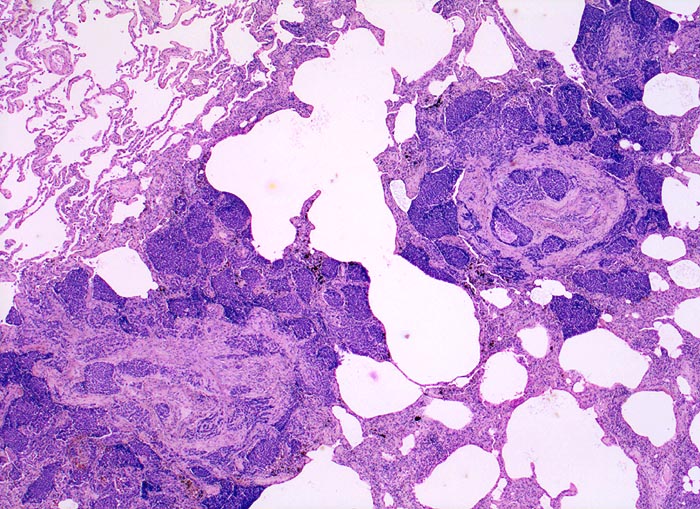

Lymphangiosis carcinomatosa

Lunge

Dunkle solide Tumorinfiltrate füllen erweiterte Lymphgefässlichtungen um einen zentralen Pulmonalarterienast. Der Tumor greift auch auf das angrenzende Parenchym über.

Metastasierendes Tumorleiden bei unbekanntem Primärtumor. Autoptisch primäres peripheres neuroendokrines Karzinom der Lunge mit ausgedehnter lymphogener und hämatogener Metastasierung.

25